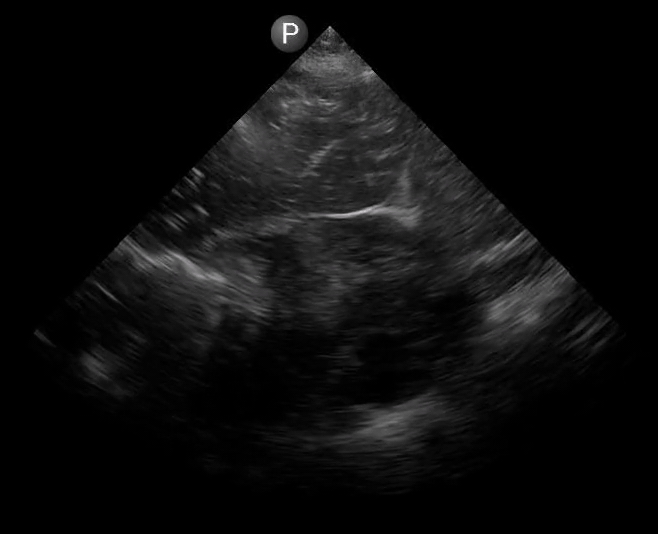

Definitions of cardiac activity and standstill vary across the literature. [14] Most definitions describe ventricular contractility and a decrease in left ventricular chamber size, though discrepancies exist with the identification of atrial or valve flutter. Ultrasound operators may also mistake movement of the chest structures with mechanical ventilation as cardiac activity. Furthermore, weak myocardial contraction, profound bradycardia, or fine ventricular fibrillation can also be confused as cardiac standstill. Examples of cardiac standstill and a weak, bradycardic rhythm are highlighted in Figure 2.

Figure 2. A) Parasternal long view with cardiac standstill. B) Subxiphoid view highlighting weak cardiac activity.

The authors would like to acknowledge Sara Damewood, MD for her review and for providing the cardiac standstill image seen in Figure 2. The authors also thank John Collins for assisting with the creation and editing of Figure 1. Last, the authors would like to thank Jessica Schmidt, MD, MPH and Dana Resop, MD, for their thoughtful review and feedback.